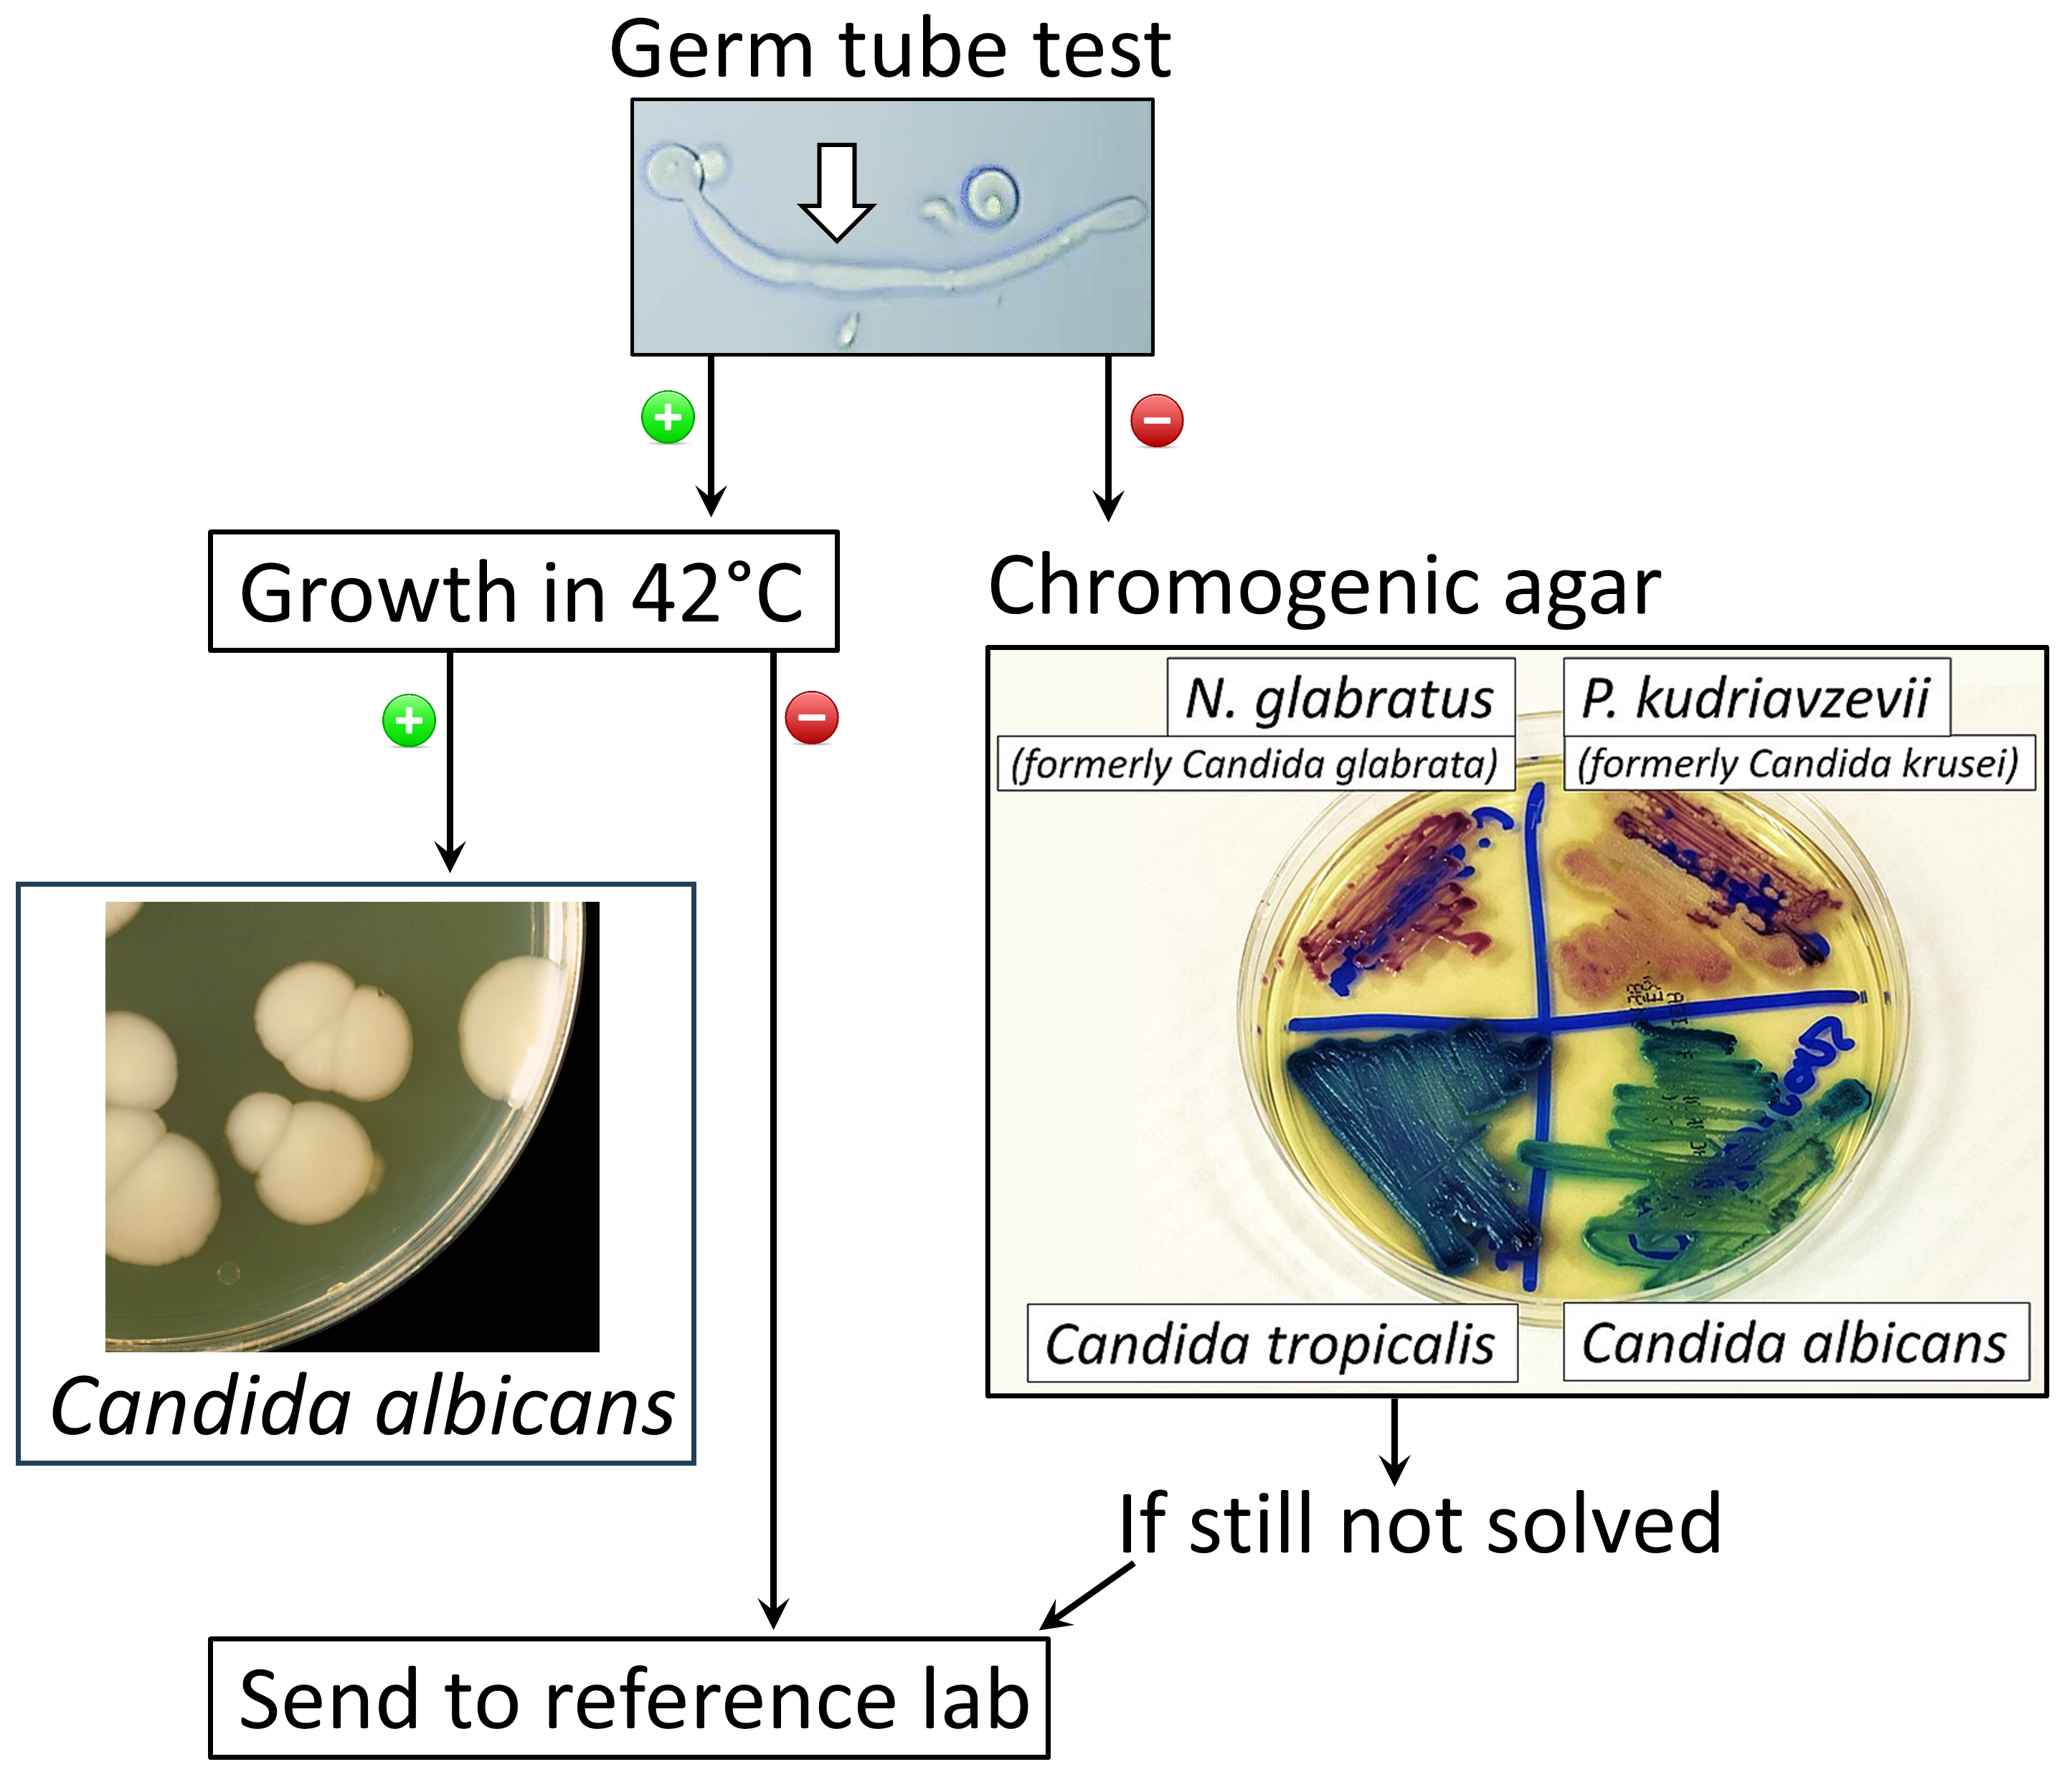

진균증 진단은 일반적으로 징후와 증상, 현미경 검사, 생검, 배양 검사, 때로는 의학 영상의 도움을 통해 이루어진다.[9]